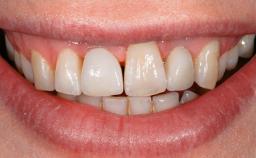

In 2004, the patient, a smoker, began dental treatment at the ACTA graduate clinic. She was a TV producer exposed to a lot of stress in her job and had a sick husband. Her maxillary teeth had been extracted, as had the mandibular canines, premolars, and molars, with the exception of tooth 34. She received a complete maxillary denture and a mandibular skeleton denture. In October 2007, her maxilla was augmented by an oral and maxillofacial surgeon; in March 2008, implants (Biomet 3i, Palm Beach, Florida, USA) were inserted at that same clinic. In 2008, the patient was presented at the Department of Oral Implantology and Prosthetic Dentistry to request restorations for her implants. An implant-supported overdenture was planned. She also asked if we could restore her occlusion with fixed prosthetics.